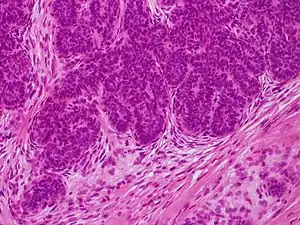

Image at left shows a trichoblastoma from a 68-year-old Caucasian male. It shows a pseudo-encapsulated, multinodular, basaloid tumor with fibrocellular stroma spanning the reticular dermis extending into subcutaneous fat (A). No epidermal connection or retraction artifact was noted. Tumor lobules were arranged as monomorphous basaloid cells in a cribriform pattern with peripheral palisading some resembling abortive hair follicles (B, F). Focally, tumor lobules exhibited squamous eddies, papillary mesenchymal bodies, and a germinative component comprising basaloid cells admixed with distinct pales cells (Zellballen) (C–E, D is an enlargement of boxed area in C).[3]